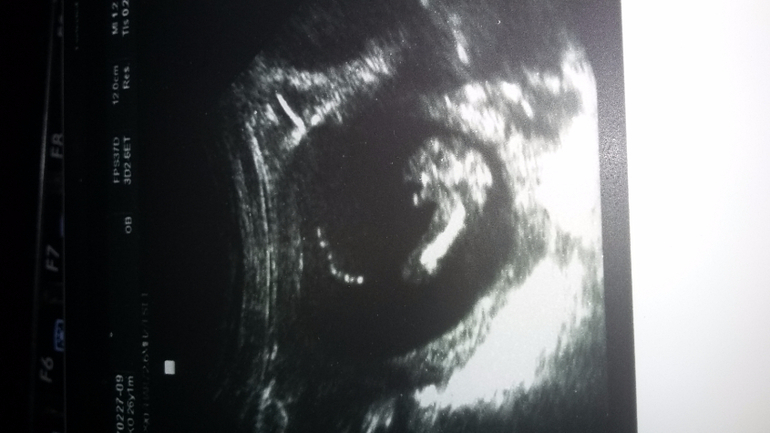

2 : 1 в пользу мальчика

Как вы тут что понимаете)))

Писюлька же торчит между ножек:)

Это вид снизу на попу. Вот это длинное - это бедро, чуть левее от него видно писюлю - выпуклость с точечкой, еще левее выпуклость маленькая - второе бедро, но его не видно, видимо ножка куда-то вверх поднята

Ааа вторая ножка поднята! Теперь поняла))

Почему не похоже-то?:) Как раз мальчишеский кадр :)

Оно то понятно что где))))может это пуповина?...)))))

Не:) Четко краник. Я так понимаю, Вы доченьку хотели. Ну кто знает, может это еще не последний ребенок, всякое в жизни бывает. И зачем-то Ваши мальчишки выбрали Вас своей мамой. Значит, Вы будете самой лучшей мамой сыночков